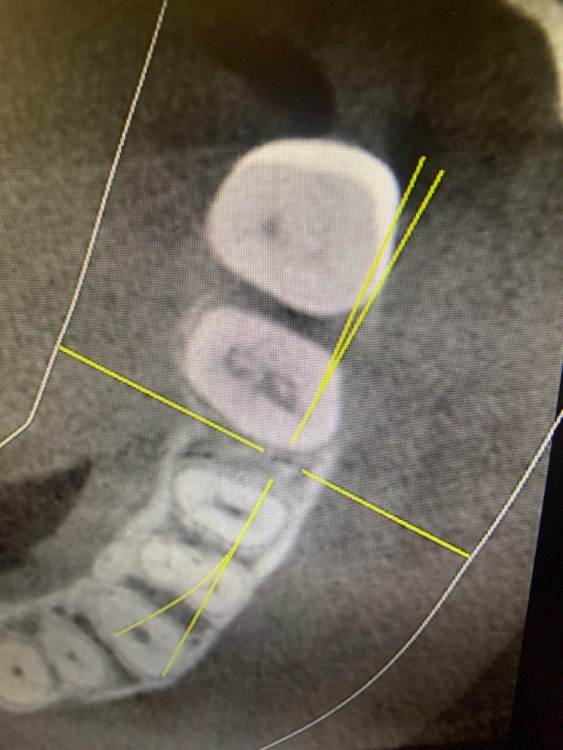

KOCTb Опубликовано 1 января, 2024 Поделиться Опубликовано 1 января, 2024 Здравствуйте коллеги. Может кто-то подскажет полезного. Пациентка. Лет 6 назад пришла с симптоматикой пульпита во втором секторе. На некоторых зубах были пломбы, без криминала. Зубы были проверены на витальность. Все живые. Пальпаторно передняя стенка ВП давала лёгкую чувствительность. Сделали КТ. Апикальных изменений не выявлено, а в пазухе слева признаки гайморита. Заполнена была бальше чем наполовину. Отправил к ЛОРу. Пролечили. Анатомическое строение не очень понравилось. С тех пор каждую зиму у неё обострение ВЧ синусита слева. Иногда даже два раза бывает. Каждый раз ЛОР в направляет к стоматологу и говорит, что гайморит одонтогенгый. Врачи рентгенологи в описании иногда там находят одонтогенгую кисту… Года два назад пациентка сходила поменяла все пломбы, на всякий пожарный. Со слов зубы все были витальные при лечении. Ну и собсвенно опять ВЧ синусит. Смущает анатомическое строение между 25 и 26 зубом. Не может ли там через периодонтальную щель «сифонить» ? Говорит между зубами иногда какой-то дополнительный дискомфорт есть. Ссылка на комментарий

KOCTb Опубликовано 15 января, 2024 Автор Поделиться Опубликовано 15 января, 2024 19 часов назад, Astronaft сказал: Здравствуйте. 6 лет назад: подробнее про симптомы пульпита? как полечили гайморит и чего добились? Анатомия действительно интересная. Интуитивно, или естественная впадина которая способствует застою либо проблемы в соустье вызывают застой и кислотный секрет лизирует самое слабое место. Опять же интуитивно, пациентке приказать зубы не трогать, не ходить выискивать проблемы. Очень подробно расспросить анамнез, в том числе что помогает, что запускает синусит. Если соустье открыто то я бы рекомендовал регулярно промывать физраствором с ЭДТА и выждать. Здравствуйте. Ну как обычно пульпитная симптоматика при ВЧ синусите. Разлитые периодические боли в верхнем секторе, с непонятной локализацией. Пальпаторно передняя стенка ВЧ пазухи давала болезненность. От 25 до 27 зуба. На КТ зубов затенение в ВЧ пазухе. Отправил тогда к ЛОРу. Подробности лечения у ЛОР врача тогда не знаю. Синуситы в холодное время года. Соустье пародонтальным зондом не выявлено. Носо-ротовая проба также отрицательная. Но тут и понятно если и есть ход, то крайне мизерный. Там слизистой завалено всё. Ссылка на комментарий